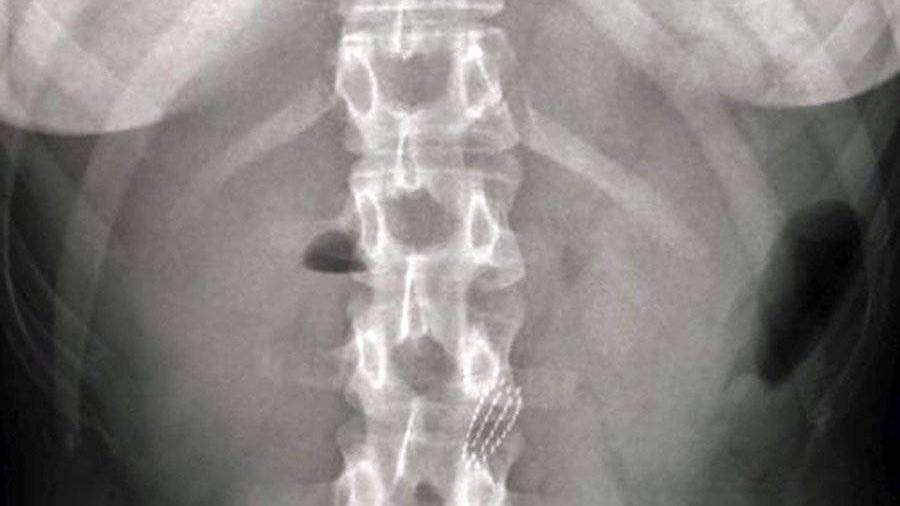

Жительница Москвы проглотила зубную щетку, когда пыталась ею протолкнуть застрявший в горле кусок колбасы. Об этом 15 июня сообщается на сайте столичного департамента здравоохранения.

Инцидент произошел во время семейного ужина. В какой-то момент 22-летняя девушка почувствовала, что в горле застрял кусок колбасы, и пошла в ванную комнату, чтобы решить проблему. Она попыталась протолкнуть кусок пищи зубной щеткой, но когда средство гигиены уперлось в него, девушка неожиданно вдохнула и вместе с колбасой проглотила и зубную щетку, пишет агентство городских новостей «Москва». После этого она выбежала из ванной и позвала на помощь, ее родители незамедлительно вызвали скорую. Пострадавшую доставили в Боткинскую больницу, пишет «Федеральное агентство новостей».

Пациентку с диагнозом «инородное тело в верхних отделах желудочно-кишечного тракта» направили в отделение эндоскопии для извлечения инородного предмета. Вся процедура заняла один час. Медики сделали петлю и эндоскопом аккуратно вытащили инородный предмет. Молодая пациентка слушала специалистов и выполняла все рекомендации докторов, сообщает телеканал «360». После этого ее отправили домой с рекомендациями наблюдаться у хирурга своей поликлиники, уточняет РИАМО.